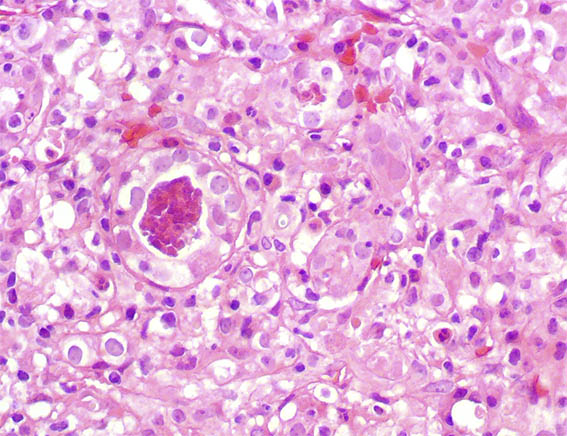

Bilateral renal biopsies were performed.See the images.

Figure 4. H&E, X400.